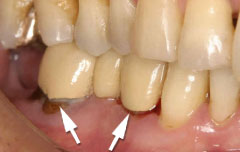

| 歯茎にプラーク(歯垢着が)と歯石の沈認められます。歯肉が腫れ、出血がありました。 | 歯科衛生士の治療と、ブラッシング技術の向上により、歯茎が引き締まり健康的な状態になりました。 | |